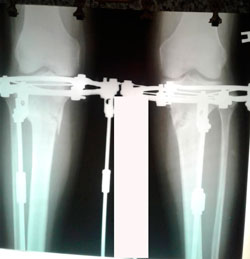

Дата операции - 16.03.2020

Дата снятия аппаратов - 30.06.2020

image-17-03-20-05-45-4-(2).jpg

image-17-03-20-05-45-1-(2).jpg